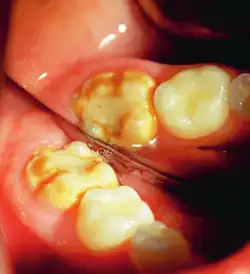

It occurs as a result of severe hypomineralization of the enamel as the enamel appears intact in the initial stages but gradually chips and fractures after the tooth erupts due to the weakened mineral content hence, leading to the formation of rough surfaces and cavities which makes the tooth highly vulnerable to undergo wear, decay and sensitivity.[26] Notably, the post-eruptive breakdown is linked to severe forms of hypomineralization like molar incisor hypomineralization (MIH).[27]

Enamel hypocalcification is characterized by visible defects in the enamel, often manifesting as white spot lesions or brown discolorations.[35] In cases such as dental fluorosis, this may include mottled patterns on the enamel surface which vary in appearance and extent based on the severity of the condition.[36] In advanced cases, the mottled appearance of the enamel can expose the underlying dentin, creating an uneven and sometimes porous surface. Though the matrix of the enamel initially forms to a typical thickness, the mineralization or calcification process is incomplete or deficient, leading to softer and structurally compromised enamel.[35]

This compromised enamel is more susceptible to staining due to its rougher surface texture and increased permeability, which allows pigments and external elements to penetrate more easily. The weakened enamel may begin to wear away, especially on the occlusal surfaces of the molars, where mechanical forces are most intense. In some individuals affected by severe enamel hypocalcification, the structural deficiencies also contribute to anterior open bite where the upper and lower front teeth do not meet when biting down. This malocclusion can further complicate both functional and aesthetic aspects of the dentition.[37]